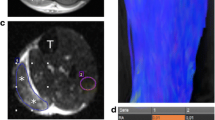

FA values from DTI20 as well as FApseudo values from models 1, 2, and 3 were clearly lower in diabetic patients than in young or age-matched controls (p < 0.001, Fig. 3b). ROC analysis revealed excellent discrimination between patients and age-matched controls by all models achieving comparable values of areas under the receiver operating characteristics curve of 0.847 (DTI20, p = 0.004), 0.854 (model 3, p = 0.003), 0.861 (model 1, p = 0.003), and 0.868 (model 2, p = 0.002; Fig. 3a). Furthermore, patients had increased ADC or ADCpseudo and RD or RDpseudo values compared to either control group (p < 0.001) in all models, while ADpseudo from models 1, 2, and 3 was only slightly higher in patients (p < 0.001 and p = 0.003; Supplementary Fig. S5). Figure 4 shows FA maps derived from DTI20 and models 1, 2, and 3 in a representative diabetic patient and healthy participant.

Fractional anisotropy (FA) map reconstructions in healthy and diabetic patients. Representative images of a healthy subject (a) and a diabetic patient (b) showing T2-weighted images of the distal sciatic nerve and corresponding color-coded fractional anisotropy (FA) maps calculated with the 20-directional standard model (DTI20) and the reduced models 1, 2, and 3. Segmentation of the nerve portion is indicated by a white contour. Insets show a magnification of the nerve. Model 1 achieves the best approximation to DTI20 in both healthy and diseased nerve tissue, while models 2 and 3 yield good but inferior accuracy

Influence of intraneural connective tissue and nerve angulation

The proportion of intraneural connective tissue was negatively correlated with absolute FA values in DTI20 and FApseudo values in all simplified datasets, showing the highest dependence in young healthy subjects (r = -0.49 to -0.32, p < 0.001 each; Supplementary Tables S3 and S4; Supplementary Fig. 6a). Accuracy was not significantly correlated with connective tissue proportions. Nerve angulation with respect to the scanner’s z-axis ranged from a median of 5.79° (range 0.31–15.8) in the median nerve to 13.30° (range 2.22–30.50) in the radial nerve (Supplementary Table S3). Only weak associations were found between nerve angulation and absolute FA or FApseudo values or accuracy (Supplementary Table 5 and Fig. S6b).

Regarding factors potentially influencing read-out parameters in a negative way, we found that smaller deviations of nerve angulation seemed to have a negligible effect on the accuracy of the simplified diffusion models. Similarly, the accuracy of the models was not found to be strongly affected by the amount of intraneural connective tissue. Instead, we found that absolute FA values decreased with more intraneural connective tissue in all models including the standard 20-vector model. Given the currently limited spatial resolution of diffusion sequences, this raises the question of whether partial volume effects may substantially contribute to the reduction of FA found in many peripheral neuropathies.